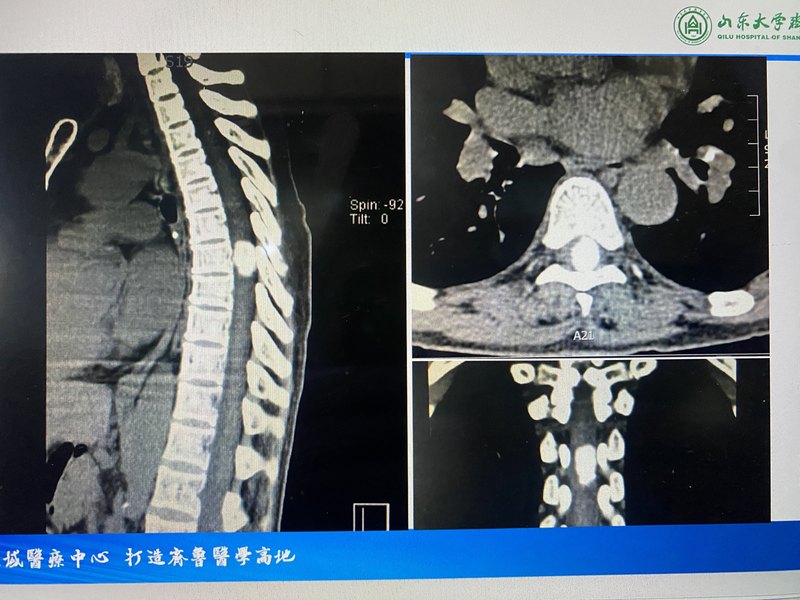

椎管內(nèi)脊膜瘤

脊膜瘤:多為良性,邊緣光滑、分界清楚,位于脊髓背外側(cè)多見(jiàn),呈廣基底與硬膜相連,包膜完整,易發(fā)生鈣化。主要為脊髓壓迫癥狀。?T1為等或稍低信號(hào),T2為等或高信號(hào)。增強(qiáng)掃描強(qiáng)化明顯,可見(jiàn)脊膜尾征,部分病例CT檢查可見(jiàn)鈣化灶。治療方式:手術(shù)治療。很多脊膜瘤是因肢體麻木無(wú)力癥狀發(fā)現(xiàn),發(fā)現(xiàn)時(shí)一般有脊髓壓迫,需及時(shí)行手術(shù)治療,手術(shù)原則是盡可能將腫瘤基底處硬膜內(nèi)層切掉,以降低復(fù)發(fā)幾率。

脊膜瘤在臨床上主要和髓外硬膜下的其他類的腫瘤進(jìn)行鑒別,其中最為常見(jiàn)的是神經(jīng)鞘瘤。在進(jìn)行影像學(xué)檢查時(shí),神經(jīng)鞘瘤通常表現(xiàn)為橢圓形、臘腸狀的腫瘤,在增強(qiáng)掃描上沒(méi)有明顯的硬脊膜強(qiáng)化,在CT也沒(méi)有明顯的鈣化。而脊膜瘤通常會(huì)有不同程度的鈣鹽沉積,形成腫瘤的鈣化甚至骨化,在進(jìn)行增強(qiáng)掃描時(shí),可以見(jiàn)到腫瘤以寬基底附著于硬脊膜,在腫瘤周邊會(huì)有明顯的硬脊膜強(qiáng)化,也就是臨床上的硬脊膜尾征。